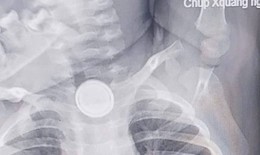

Cụ ông 90 tuổi nguy kịch sau bữa cơm tối

Camera bệnh viện - 06/10/2025 17:07SKĐS - Bệnh viện Bệnh Nhiệt đới Trung ương vừa cứu sống thành công cụ ông N.V.S (90 tuổi, ở Hà Nội) bị tắc nghẽn đường thở trong lúc ăn tối.